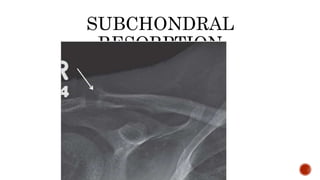

FINDINGS

 Osteopenia

 Subperiosteal resorption: classically along radial aspects of phalanges

 Floating tooth

 Subchondral resorption (lateral end of clavicles, pubic symphysis, sacroiliac joints)

 Subligamentous resorption(ischial tuberosity, trochanters)

 Brown tumors(more common in primary)

 Salt and pepper skull

 Rugger jersey spine

 Secondary and tertiary hyperparathyroidism may be associated with osteosclerosis of

renal osteodystrophy and osteomalacia of vitamin D deficiency

 Superior and inferior rib notching may be seen

SUBPERIOSTEAL RESORPT

SUBCHONDRAL

RESORPTION